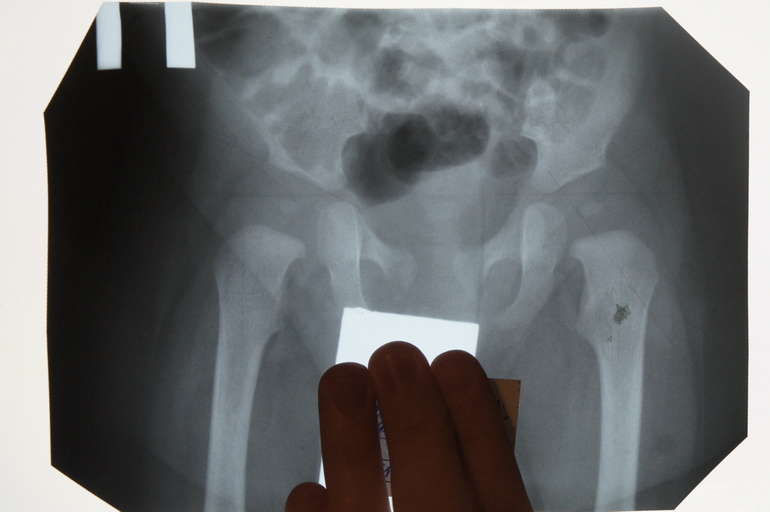

Из больницы мы вышли с кучей назначений - "до двух часов в день" (т.е. по два часа, если дите совсем не разорется раньше) укладки. Сапожки на стопы, платки на руки, самая сложная, когда ладошки (мааленькие ладошки, попробуй разожми) примотаны к плоским дощечкам и рука к такой палке, которая еще уходит на тело... И широкое пеленание. Четыре штуки по 2 часа в день... При том миографию обещали сделать через 2 месяца, когда ляжем и немного подрастем, а врач, который принимал роды и многие другие, говорили, что все у нас нормально. Внешне у ребенка все было в порядке, руку он поднимал и она была даже больше здоровой благодаря стимуляции в больнице. Невролог в поликлинике вообще руку перепутал... Я была не уверена, что не мучаю дитя напрасно. Надо ли говорить, что при первой попытке широченным бинтом сделать укладку я наревелась вместе с дитем и забросила все эти назначения вместе с широким пеленанием заодно? Неким оправданием мне может служить то, что я носила его в слинге. По три часа в день на прогулке, иногда даже больше - и точно больше, чем назначили широкое пеленание. Но когда подошла наша очередь на массаж и массажистка, которой я обмолвилась про слинг, сказала ни в коем случае не носить несидящего ребенка вертикально более 20 минут в день, я решила ей верить, перестала пользоваться слингом, и не стала ничего делать взамен... УЗИ в поликлинике пропустила, потому что о куче разных назначений участковому педиатру надо было напоминать, а об этом напомнить я забыла, а потом думала, что скоро лягу повторно в больнице, и узи нам сделают там, а госпитализацию пропустила по своей глупости... В общем, в 5 и 10, за день до выписки, нам сделали рентген и поставили дисплазию. Какая степень, что там - фиг его знает. Ортопед в больнице такой странный неразговорчивый дядька - когда приходил смотреть ребенка, то молча посмотрел, развернулся и ушел. Я задала ему один из многочисленных заготовленных вопросов в спину - спина закрыла за собой дверь, зато зашедшая в этот момент в палату заведующая почему-то приняла этот вопрос на свой счет и наругалась на меня, потому что я уже задавала ей другой вопрос на ту же тему, и она мне уже отвечала... В общем, было весело. В день выписки у ортопедов был операционный день, и объясняла мне все лечащий врач. Прописали шину Виленского на круглосуточное ношение на 6 месяцев, потом повторный рентген. Я спросила у врача, что там с суставами - она ответила, что углы не те с обеих сторон. Какие углы, не сказала. Надела самую маленькую шину ребенку на бедра (как мне показалось) и сказала, что размер нам подходит, и чтобы я не переживала - ребенок быстро привыкнет, с этой шиной и сядет, и пойдет... Отдельно сказала, что нам нужна шина только зацепинская, с шарнирами, потому что в ней двигаться лучше, что они переехали, и дала адрес. Что подушка Фрейка нам уже не пойдет, потому что надо, чтобы ребенок двигался, а он у меня того и гляди поползет.